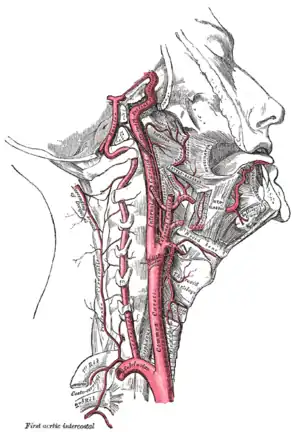

Head and neck

- Carotid pulse: located in the neck (carotid artery). The carotid artery should be palpated gently and while the patient is sitting or lying down. Stimulating its baroreceptors with low palpitation can provoke severe bradycardia or even stop the heart in some sensitive persons. Also, a person's two carotid arteries should not be palpated at the same time. Doing so may limit the flow of blood to the head, possibly leading to fainting or brain ischemia. It can be felt between the anterior border of the sternocleidomastoid muscle, above the hyoid bone and lateral to the thyroid cartilage.

- Facial pulse: located on the mandible (lower jawbone) on a line with the corners of the mouth (facial artery).

- Temporal pulse: located on the temple directly in front of the ear (superficial temporal artery).